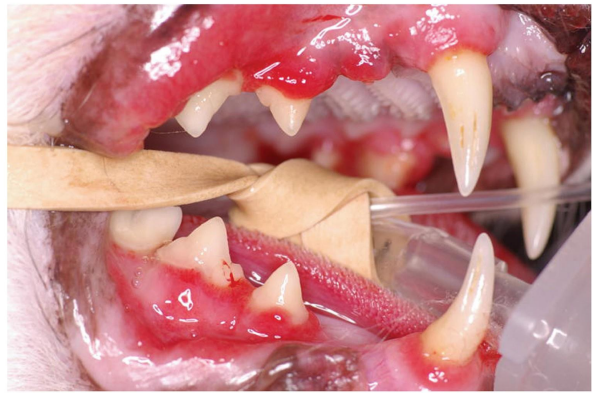

FCGS = Feline chronic gingivostomatitis

CUPS = Canine ulcerative paradental stomatitis

Immune background?

Painful!

Severe gingivitis + stomatitis (oral mucosal

inflammation) (+/- ulcers), often only minimal amounts of plaque present.

For owners, “plaque allergy” might be an OK simplification sometimes to include.

Not the same disease in dog and cat but similar enough to each other. It’s not exactly known why they happen.

Tx: COHAT, impeccable homecare, use of

medicines, extraction of (all or most) teeth.